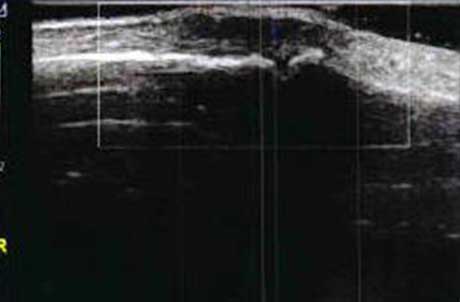

2、清晰显示滑膜异常形态,定量评估RA炎性

类风湿性关节炎以滑膜炎为基本病理改变,超声可观测到关节暗区的范围及厚度,判断有无滑膜增厚、显示不同程度的滑膜均匀或不均匀增厚,分辨滑膜呈绒毛状、团状或结节状结构向关节腔突起的形态。通过对滑膜厚度、水肿、炎性细胞浸润状况的分级、定量评估RA关节内滑膜的炎性程度。

超声探测滑膜增生 分级

• Ⅰ级滑膜增生

轻度滑膜增生,不超过骨面 点连线

• Ⅱ级滑膜增生

滑膜增生超过骨面 点连线,呈绒毛状,但不越过骨干

• Ⅲ级滑膜增生

滑膜增生超过骨面 点连线,呈团块状延伸超过一侧骨干